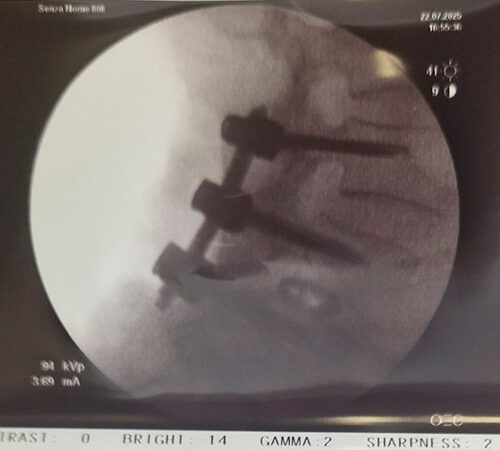

DIAGNOSI:

STENO-INSTABILITA’ LOMBARE MEDIANA

Risonanza magnetica lombare pre-operatoria

Intervento chirurgico eseguito:

PROCEDURA PLIF: POSTERIOR LUMBAR INTERBODY FUSION

Stabilizzazione vertebrale percutanea L4-L5 + introduzione di cage intersomatica PLIF Radiografia lombare post-operatoria